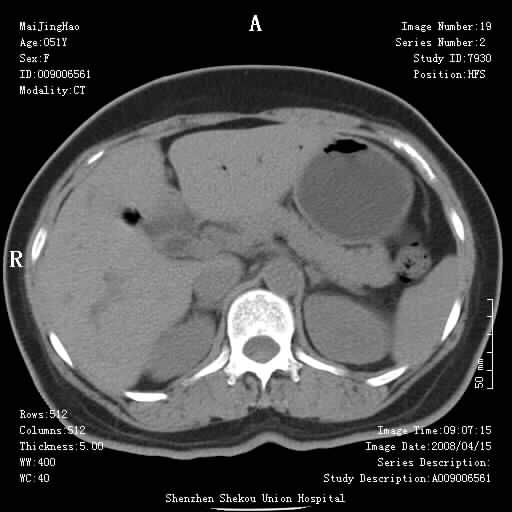

以下是引用余辉在2008-4-26 8:55:00的发言:[br]患者有结石史,此次腹痛4小时,胆总管全程扩张,应有胆总管末端梗阻,此次仍考虑胆结石症,积气不外两种原因,一种是结石下移时肠道内气体逸入,其次为产气菌感染。(倒数第三幅图像于扩张之胆总管末端似可见稍高密度影,考虑为结石影)

以下是引用听蝉观竹在2008-4-26 11:41:00的发言:[br]胆道手术分两种情况:[br]1、如果仅仅做胆囊切除手术,肝内胆管不会积气,只会出现胆总管代偿扩张,因为奥迪氏括约肌依然功能正常胆道与外界并不相通;[br][br]2、胆囊切除+胆总管空肠吻合手术(即roux-y式),则肝内胆管会出现积气,只是因为胆管与小肠相通,气体来源于小肠。这是临床十分常见的手术。[br][br]这个病例应该是胆囊切除+胆总管空肠吻合手术,是正常手术后表现,并不是胆道感染的表现。